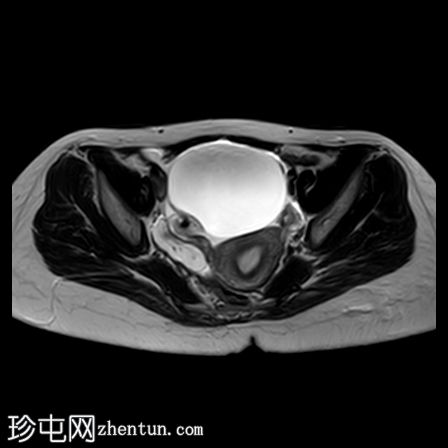

轴位

T1加权像

右侧卵巢增大,卵泡呈周边排列。

附件血管蒂扭转(漩涡征)。

右侧附件旁可见一较大的、边界清晰的盆腔囊性病变,向右倾斜,提示为卵巢旁囊肿。

本病例展示了卵巢扭转的典型影像学特征,包括卵巢增大、卵泡呈周边移位、卵巢向内侧偏移以及特征性的漩涡征。

在这种情况下,较大的卵巢旁囊肿被认为是发生卵巢扭转的高危因素。如果卵巢旁囊肿较大(>5厘米)或活动度较大,其重量/活动度增加会牵拉附件,导致卵巢和输卵管发生扭转。